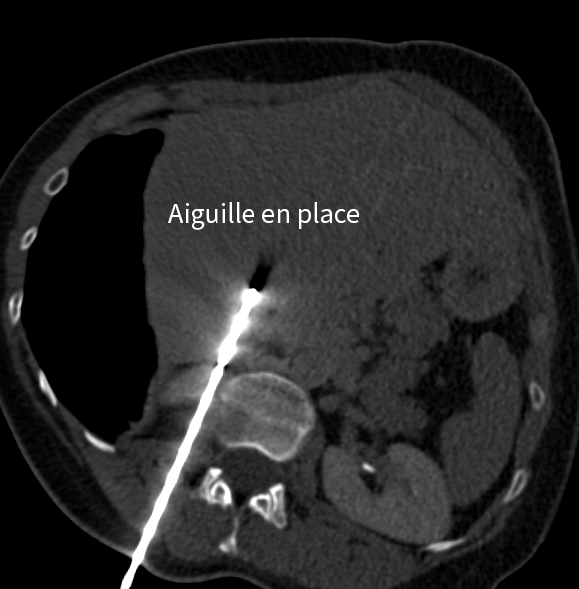

La thermoablation percutanée repose sur un principe simple : détruire la tumeur par la chaleur ou le froid, en introduisant une aiguille directement dans la lésion sous guidage radiologique (scanner ou échographie).

Focus : déroulement d'une intervention

Le geste consiste à :

• repérer précisément la lésion grâce à l’imagerie,

• insérer une ou plusieurs aiguilles,

• appliquer le traitement thermique adapté,

• vérifier l’efficacité immédiate.

Traitement hépatique par micro-ondes

Dans un second temps, la métastase hépatique est traitée par thermoablation micro-ondes, avec protection des organes voisins grâce à une technique d’hydrodissection.

Images du traitement des organes (poumon et foie) avant, pendant et après le traitement.